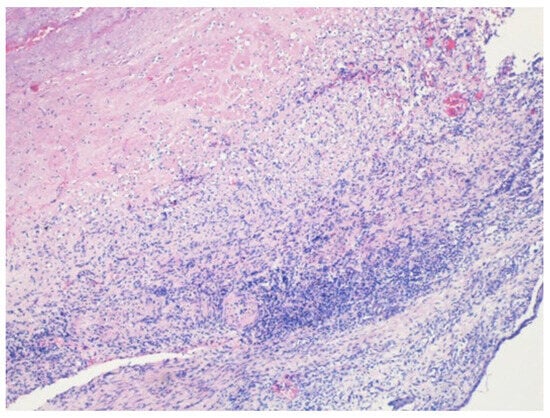

Tuberculous Aneurysm of the Thoracic Aorta: A Diagnostic and Therapeutic Challenge in the Modern Era

Introduction: Tuberculous aneurysm of the thoracic aorta (TBAA) is an extremely rare but potentially fatal manifestation of tuberculosis (TB). Clinical presentation may include hemoptysis in the absence of parenchymal lung abnormalities. Case report: We presented a 62-year-old male with cough, chest pain, [...] Read more.

Introduction: Tuberculous aneurysm of the thoracic aorta (TBAA) is an extremely rare but potentially fatal manifestation of tuberculosis (TB). Clinical presentation may include hemoptysis in the absence of parenchymal lung abnormalities. Case report: We presented a 62-year-old male with cough, chest pain, and minimal hemoptysis. Diagnostic evaluation confirmed an aneurysm of the descending thoracic aorta at a site previously treated with endovascular repair, with no imaging findings suggestive of pulmonary TB. Bronchoscopy revealed blood in the main bronchi without an identifiable endobronchial source. The diagnosis of TB was established by polymerase chain reaction (PCR) testing of bronchial aspirate obtained during bronchoscopy. Emergency surgical intervention was recommended because of an impending aortic rupture, but the patient declined surgery. Standard antituberculous therapy was initiated, and the patient subsequently developed drug-induced liver injury, prompting temporary cessation of treatment. The clinical course was later complicated by the development of an aortoesophageal fistula (AEF), with significant implications for prognosis. Conclusions: Early recognition of TBAA, along with a multidisciplinary approach that integrates advanced diagnostic modalities, timely vascular intervention, and carefully managed antituberculous therapy, is essential to reduce mortality and optimize treatment outcomes. Full article

Show Figures

Figure 1